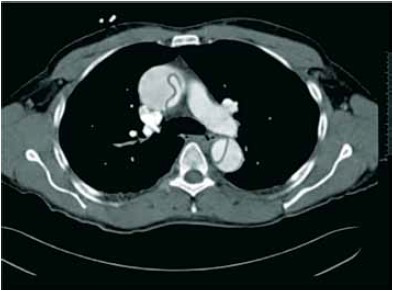

Paciente de 56 anos, sexo feminino, portadora de hipertensão arterial, com episódio de síncope após realizar esforço evacuatório. Chega ao pronto atendimento após 20 minutos.

Ao exame fisico:

– Rebaixamento do nível de consciência, escala de coma de Glasgow 5.

– Ritmo cardíaco: sopro diastólico aspirativo e em decrescendo.

– Frequência cardiaca: 120 bpm.

– Pressão arterial (MSD): 90 x 54 mmHg.

– MV+ difusos diminuidos em bases.

– Pulso radial à esquerda filiforme menor que à direita.

Após realização das medidas iniciais na sala de emergência, realizou uma tomografia de torax.